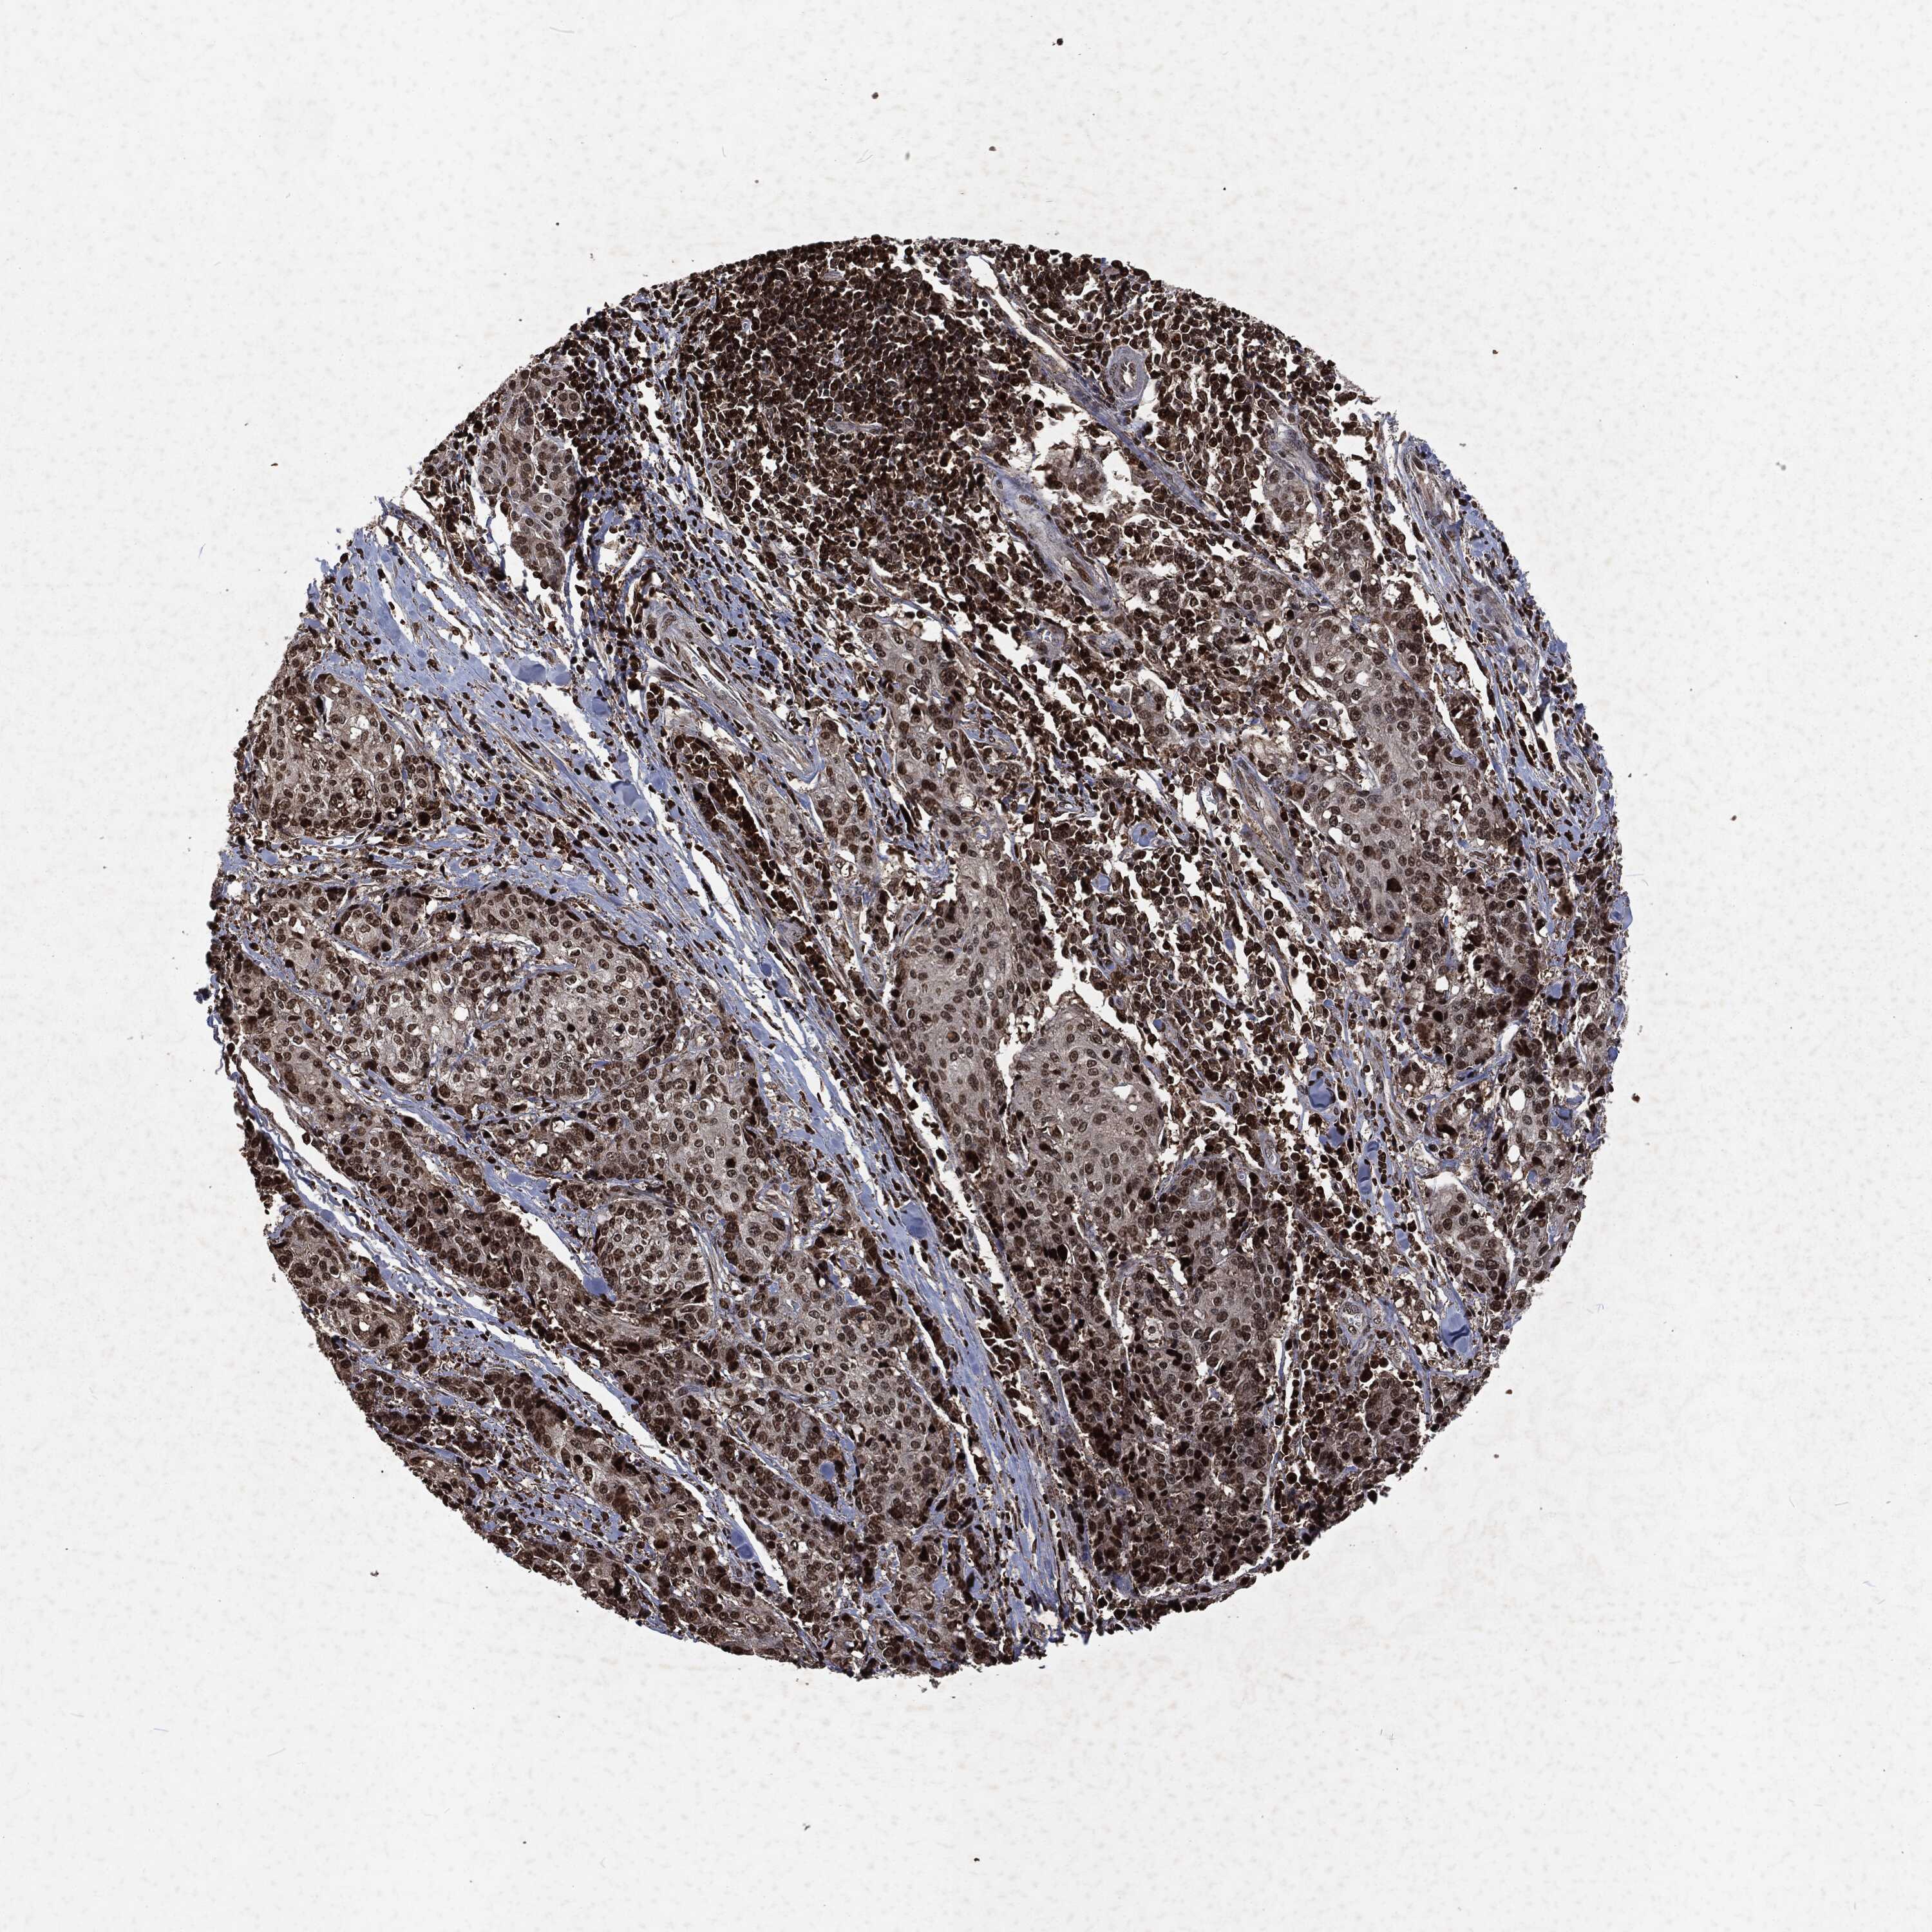

PANCREATIC CANCER - Protein expressioni

A mouse-over function shows sample information and annotation data. Click on an image to view it in a full screen mode. Samples can be filtered based on level of antibody staining by selecting one or several of the following categories: high, medium, low and not detected. The assay and annotation is described here.

Note that samples used for immunohistochemistry by the Human Protein Atlas do not correspond to samples in the TCGA dataset.

Antibody stainingi

Antibody staining in the annotated cell types in the current human tissue is reported as not detected, low, medium, or high, based on conventional immunohistochemistry profiling in selected tissues. This score is based on the combination of the staining intensity and fraction of stained cells.

Each image is clickable and will lead to virtual microscopy that enables deeper exploration of all samples and also displays staining intensity scores, fraction scores and subcellular localization as well as patient and tissue information for each sample.

Antibody HPA069985

Antibody CAB005883

Antibody CAB078687

Antibody CAB080398

Staining

High

Medium

Low

Not detected

Intensity

Strong

Moderate

Weak

Negative

Quantity

>75%

75%-25%

<25%

None

Location

Nuclear

Cytoplasmic/membranous

Cytoplasmic/membranous,nuclear

Adenocarcinoma, NOS

Adenocarcinoma, metastatic, NOS